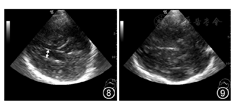

③侧脑室平面:将探头从中脑平面向上倾斜大约25°是侧脑室平面(图8)。此平面可观察侧脑室宽度,测量侧脑室额角距离:20~60岁<17 mm,≥60岁<20 mm。

④后颅凹小脑平面:探头从中脑平面向背侧旋转45°并向小脑方向倾斜10~15°为后颅凹小脑层面(图9)。此平面观察小脑齿状核有无异常回声信号,第四脑室有无异常扩大。